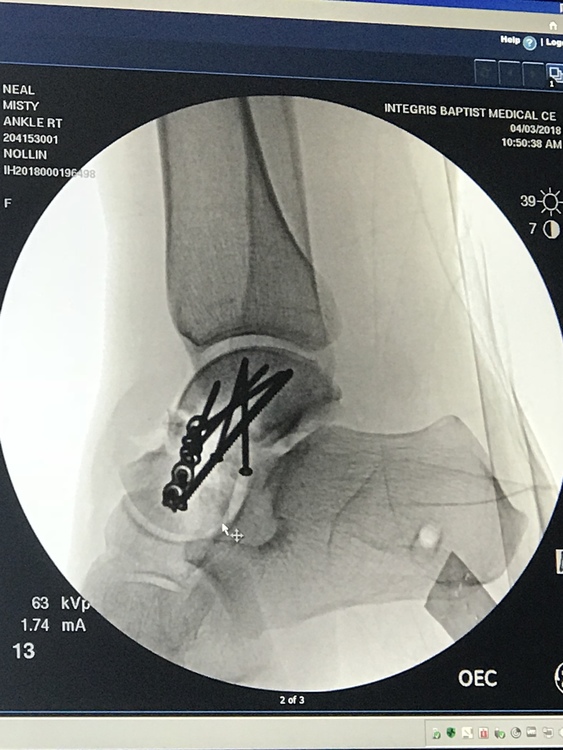

From nyfracture.com

Talus fractures (foot) New York Fracture Care Fracture Talus Treatment Treatment plan • place in temporary splint once talar neck fracture reduced • time to definitive fixation not related to increased risk of avn •. A joint called the mediotarsal separates your hindfoot from your midfoot. The lisfranc joint separates your midfoot from your forefoot. Find out how to tell if your ankle is broken (fractured) and when to get. Fracture Talus Treatment.